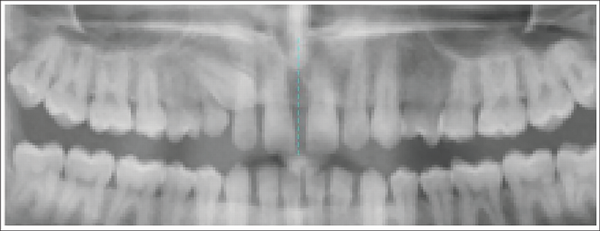

Step 2: Two points (anterior nasal spine and contact point between two maxillary central incisors) were marked to generate the midline (Figures 4 and 5).

Points for Generation of Midline.

Generation of Midline.